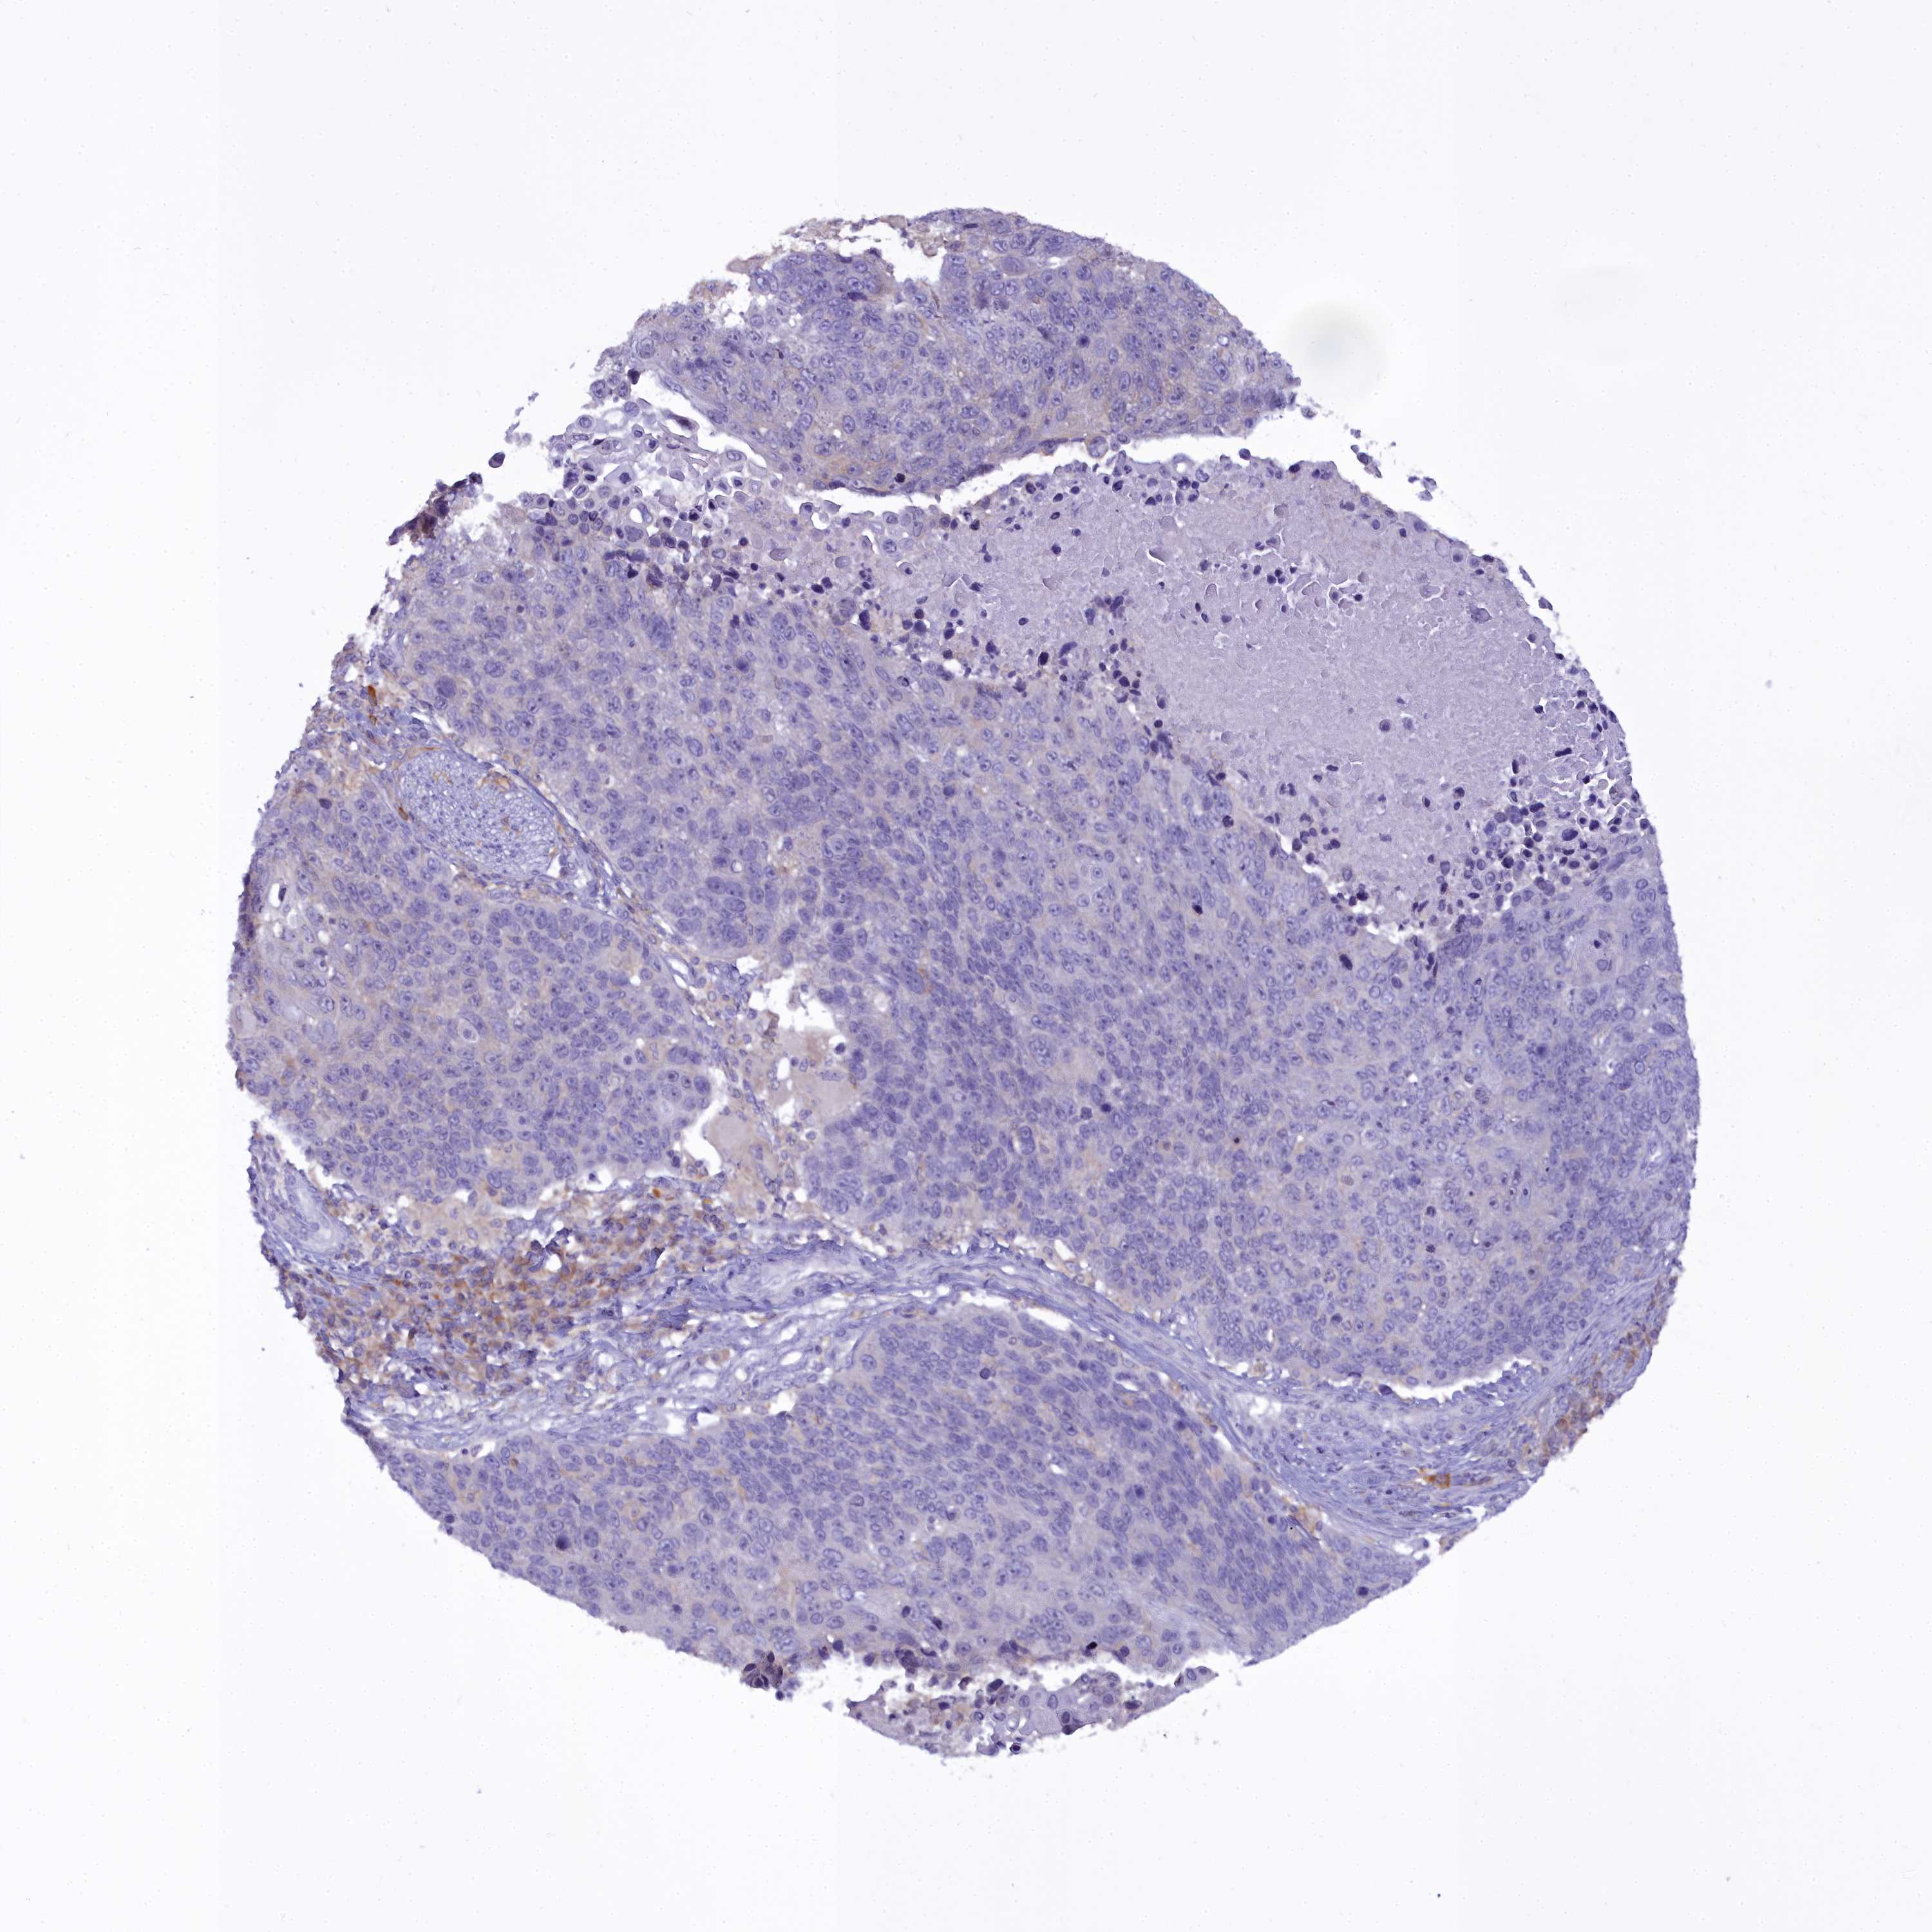

CANCER LUNG CANCER Show tissue menu

LUAD TCGA LUAD VALIDATION LUSC TCGA LUSC VALIDATION PROTEIN LUAD CPTAC PROTEIN LUSC CPTAC PROTEIN EXPRESSION

ANTIBODIES

AND

VALIDATION